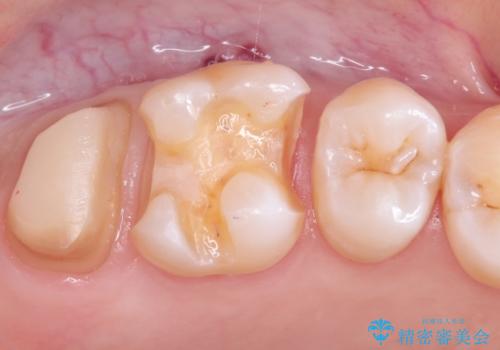

- 虫歯の治療を希望され来院された患者様です。

根管治療を行いオールセラミッククラウンによる治療を行いました。(根管治療は林先生に依頼)

歯肉の下にも虫歯が広がっており歯周外科を行った後、被せもの治療を行いました。